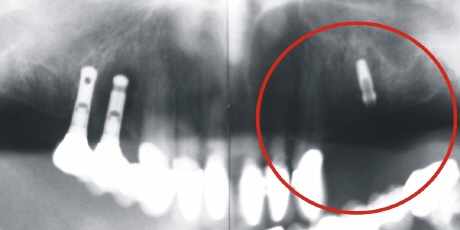

Ein Beispiel einer statischen Fehlplanung:

Implantation

Links auf dem Röntgenbild sieht man zwei bereits versorgte Implantate. Rechts wurden zwei neue Implantate eingebracht. Man beachte rechts eine bis zur Kauebene (grüne Linie) zu überbrückende erhebliche Strecke durch den späteren Zahnersatz.

Die Implantate haben keine ausreichende Länge und keinen ausreichenden Durchmesser.